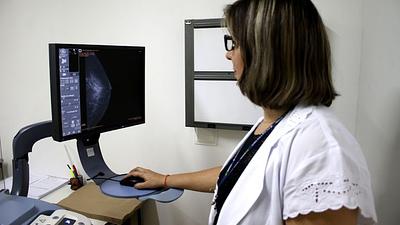

Especialista mostra importância da mamografia para prevenir câncer de mama

De acordo com o Inca, a taxa de mortalidade por câncer de mama, ajustada pela população mundial, atingiu 11,84 óbitos por 100 mil mulheres, em 2020, com as maiores taxas registradas no Sudeste e no Sul, da ordem de 12,64 e 12,79 óbitos por 100 mil mulheres, respectivamente.